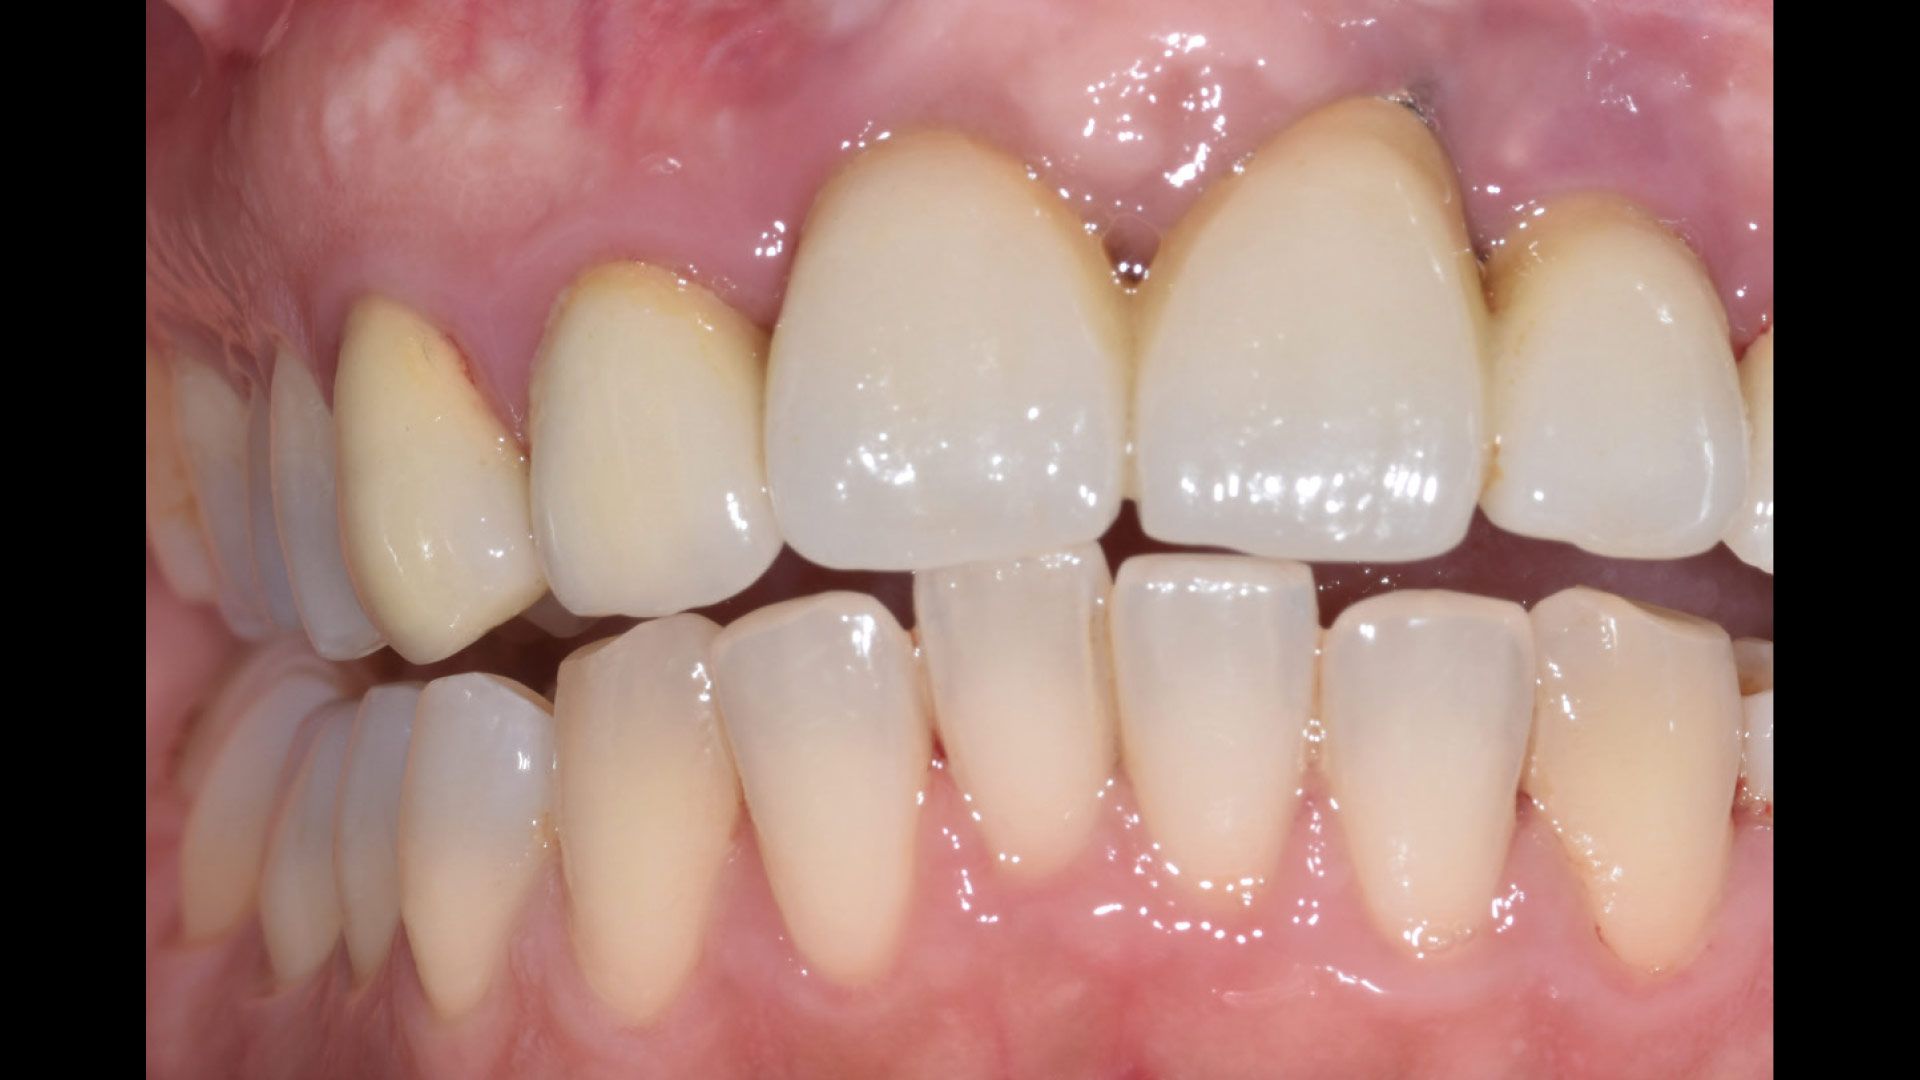

Lo studio è stato condotto presso studi dentistici privati con sede a Roma e Como. Sono stati reclutati 27 pazienti e divisi in gruppo 1 (applicazione di gel a base di clorexidina nei siti con mucosite perimplantare), gruppo 2 (applicazione di gel a base di Ozono) e gruppo 3 controllo (senza utilizzo di gel topici). Al baseline (T0) si è proceduto a valutare lo stato clinico dell’elemento implantare attraverso foto e radiografie periapicali, è stato poi rilevato l’indice di sanguinamento (Gengival Index) e successivamente è stato eseguito un debridement sub-gengivale tramite l’utilizzo di Glicina. Per il trattamento domiciliare ai pazienti sono stati consegnati gel a base di Ozono o di Clorexidina al 1% da applicare nei siti tramite lo scovolino. A T1(a 1 mese da T0) e a T2 (a 3 mesi da T0) sono state ripetute le stesse valutazioni e le stesse manovre professionali (Figg. 1a-6).

Nei pazienti afferenti al primo gruppo tra T0 e T1 si è osservato una significativa riduzione del sanguinamento al sondaggio, peggiorato poi in T2 successivamente all’interruzione dell’applicazione del gel. Nel secondo gruppo si è avuta una costante riduzione del sanguinamento al sondaggio tra T0 e T1, continuata anche in T2. In fine nel gruppo controllo il sanguinamento al sondaggio tra T0 e T1 è risultato essere incostante, così come in T2 dove non sempre vi è stato un miglioramento dell’indice di sanguinamento.

L’utilizzo di gel a base di Clorexidina e di Ozono ha portato a una regressione del sanguinamento al sondaggio nei gruppi 1 e 2, mentre nel gruppo di controllo si è registrata una persistenza del sanguinamento. Non ci sono state differenze significative tra i gruppi nel sanguinamento iniziale, ma nel tempo T2 si è osservata una recidiva della patologia nei pazienti che utilizzavano gel a base di Clorexidina, mentre non è stata riscontrata alcuna recrudescenza nei pazienti trattati con Ozono. Lo studio supporta l’uso dell’Ozono nel trattamento della mucosite, ma sono necessari ulteriori trial per un approccio condiviso e validato scientificamente.

Figg. 1a, 1b - Gruppo 1: elemento 46, immagine acquisita a T0; Fig. 2 - Gruppo 1: elemento 46, immagine acquisita a T1; Fig. 3 - Gruppo 1: elemento 46, immagine acquisita a T2; Figg. 4a, 4b - Gruppo 2: elemento 11, immagine acquisita in T0; Fig. 5 - Gruppo 1: elemento 11, immagine acquisita in T1; Fig. 6 - Gruppo 2: elemento 11, immagine acquisita in T2.